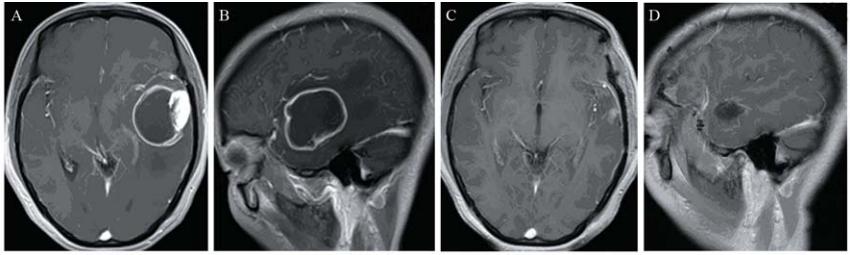

各组患者术后均定期复查头颅CT或MRI及血 常规,以了解患者手术后恢复及肿瘤复发情况, 术后定期行Karnofsky评分以评价患者术后的生存 质量。每周进行一次血常规检查,每隔4周检查 肝、肾功能及常规体检,以评价药物毒性和患者 耐受性,进行临床评价,以便调整用药,直至给 药结束为止。每4~6周复查头颅CT或者MRI检查 以判定肿瘤生长情况见图1~图3。不良反应以主观 症状和客观体征评价为主,按WHO标准分为0~Ⅳ 度。

A,B: enhanced MRI simulation before operation. There was an obvious enhancement with irregular margin in the left temporal lobe. C,D:enhanced MRI simulation 3 months after operation. There was no obvious enhancement in the left temporal lobe 图1 56岁男性间变性少突-星形细胞瘤(WHO Ⅲ级)患者手术前后增强MRI对比 Figure 1 Comparison of enhanced MRI simulation of a 56 years old male with anaplastic oligoastrocytoma(WHO grade Ⅲ)before and after operation |

A,B:enhanced MRI simulation before operation. There was a large cystic lesion with obvious enhancement of the cystic margin in the right parietal lobe.C,D:enhanced MRI simulation 3 years after operation. There was no obvious enhancement in the right parietal lobe 图2 42岁女性间变性星形细胞瘤(WHO Ⅲ级)患者手术前后增强MRI对比Figure 2 42Comparison of enhanced MRI simulation of a 42 years old female with anaplastic astrocytoma(WHO grade Ⅲ)before and after operation |

A,B:enhanced MRI simulation before operation. There was a large cystic lesion with obvious enhancement of the cystic margin in the left temporal lobe. C,D:enhanced MRI simulation 3 months after operation. There was no obvious enhancement in the left temporal lobe 图3 40岁女性间变性星形细胞瘤(WHO Ⅲ级)患者手术前后增强MRI对比Figure 3 Comparison of enhanced MRI simulation of a 40 years old female with anaplastic oligoastrocytoma(WHO grade Ⅲ)before and after operation |